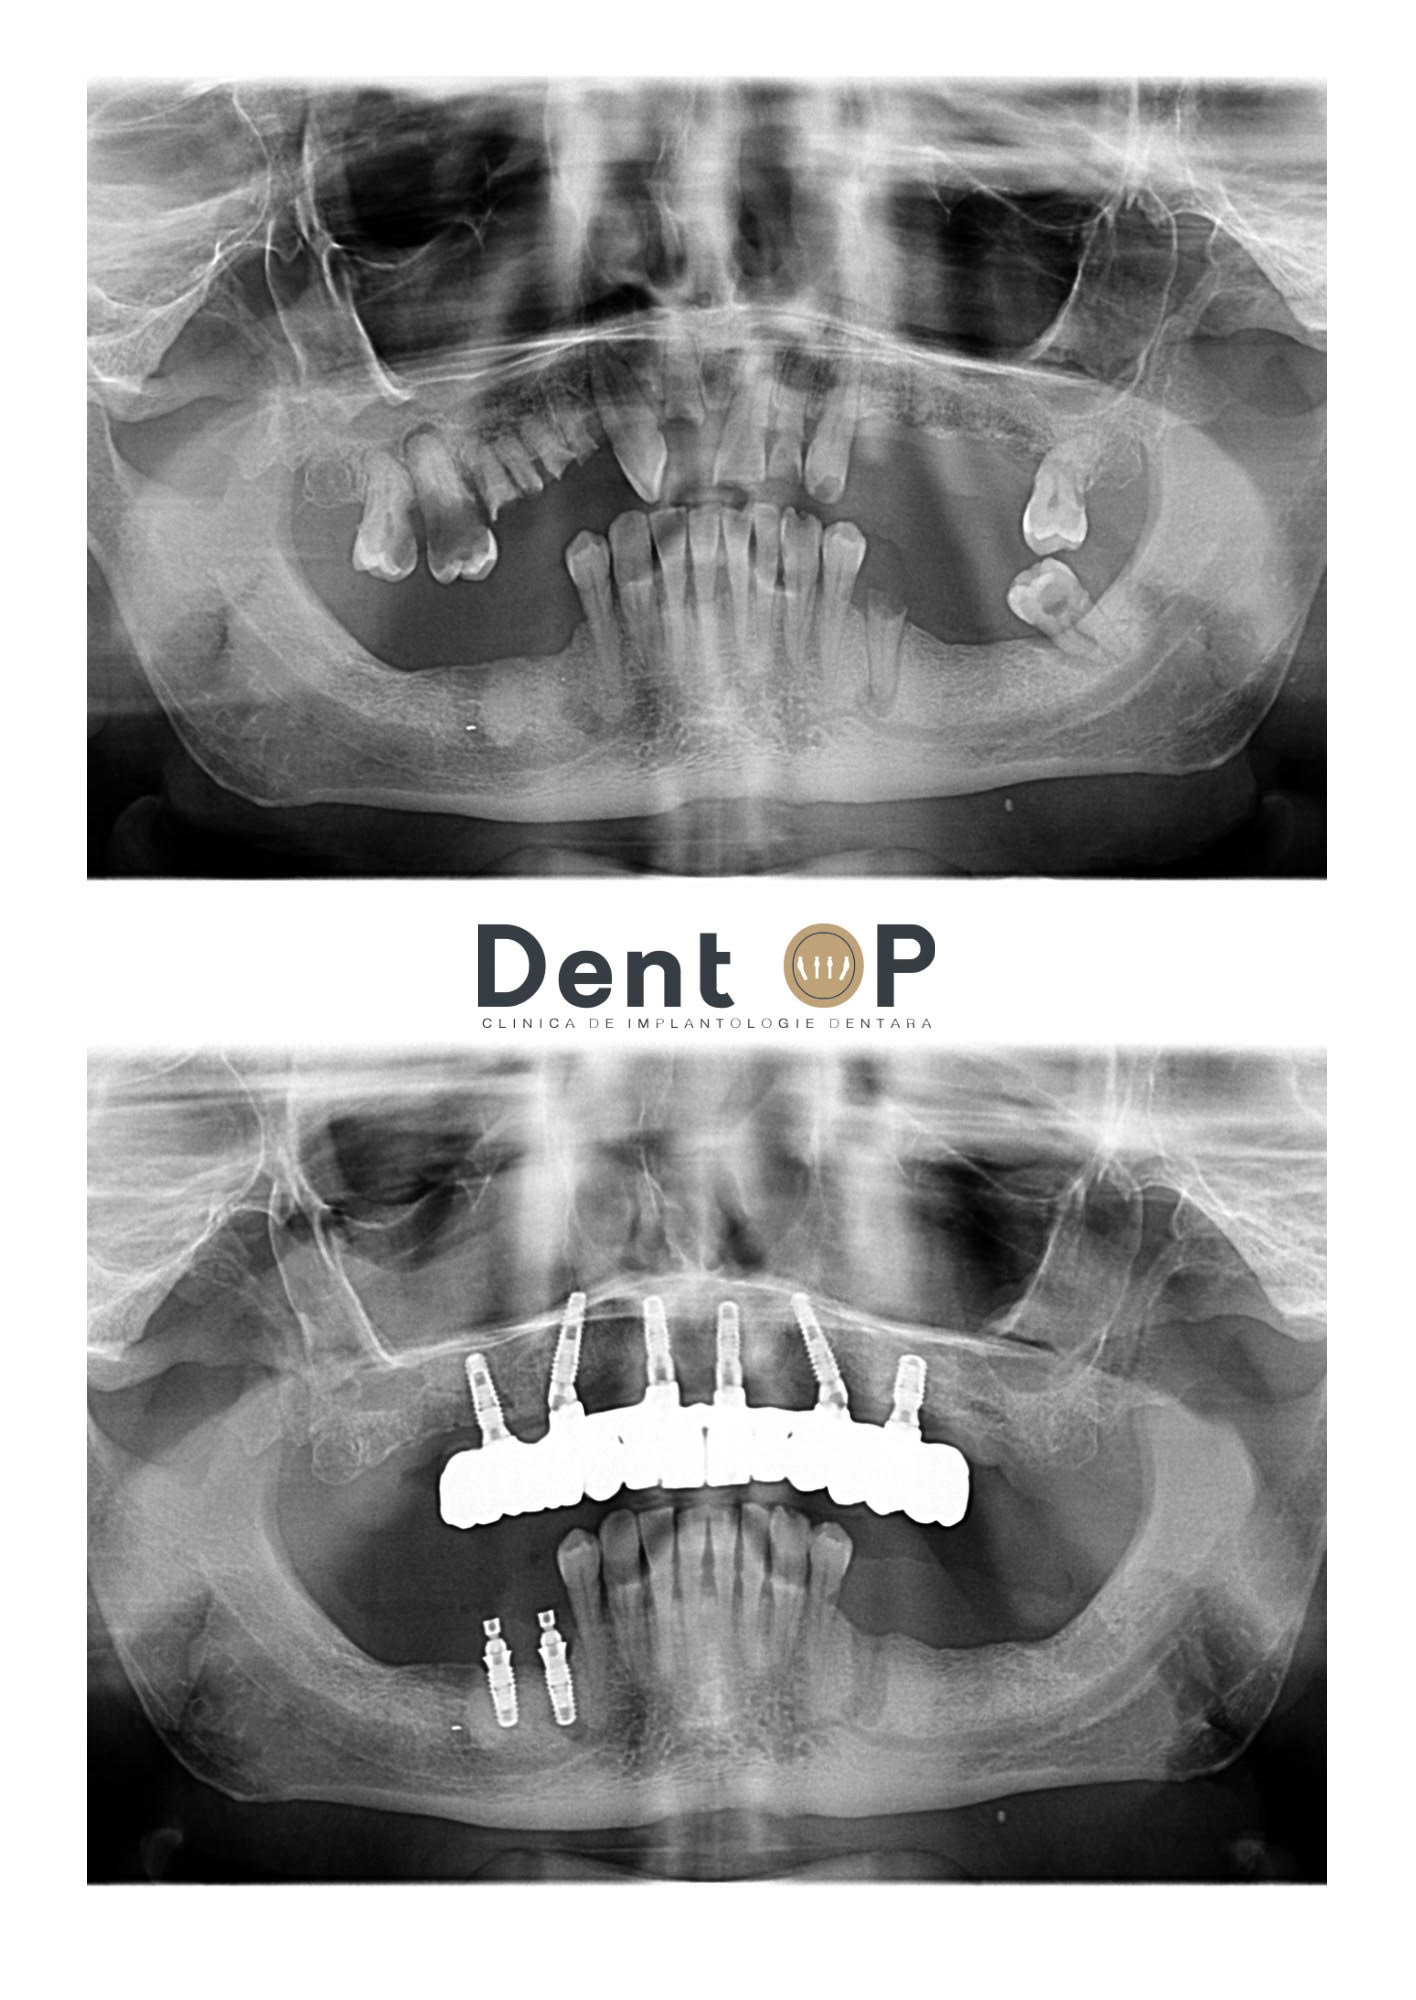

Domnul I. este un pacient care s-a prezentat de mai multe ori la Clinica de Implantologie Dentară DentOP. După ce cariile i-au afectat dantura la maxilar, domnului Ionescu i-a fost reabilitată arcada de sus cu ajutorul a 6 implanturi dentare pe care s-au pus la doar 24h și implanturile provizorii.

La mandibulă, mulți dintre dinți au putut fi salvați cu ajutorul tratamentelor endodontice. Acolo unde nu s-a mai putut salva,în partea stângă a mandibulei au fost adăugate două implanturi dentare.